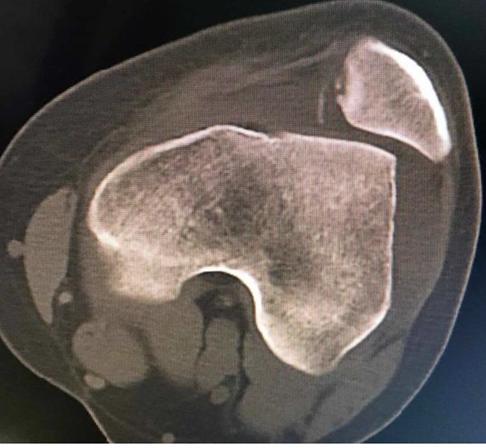

膝关节CT5. 康复训练:在恢复期间,患者应进行针对性的康复训练,如加强膝关节周围肌肉的力量训练、提高关节灵活性等。这有助于减少再次脱位的可能性。